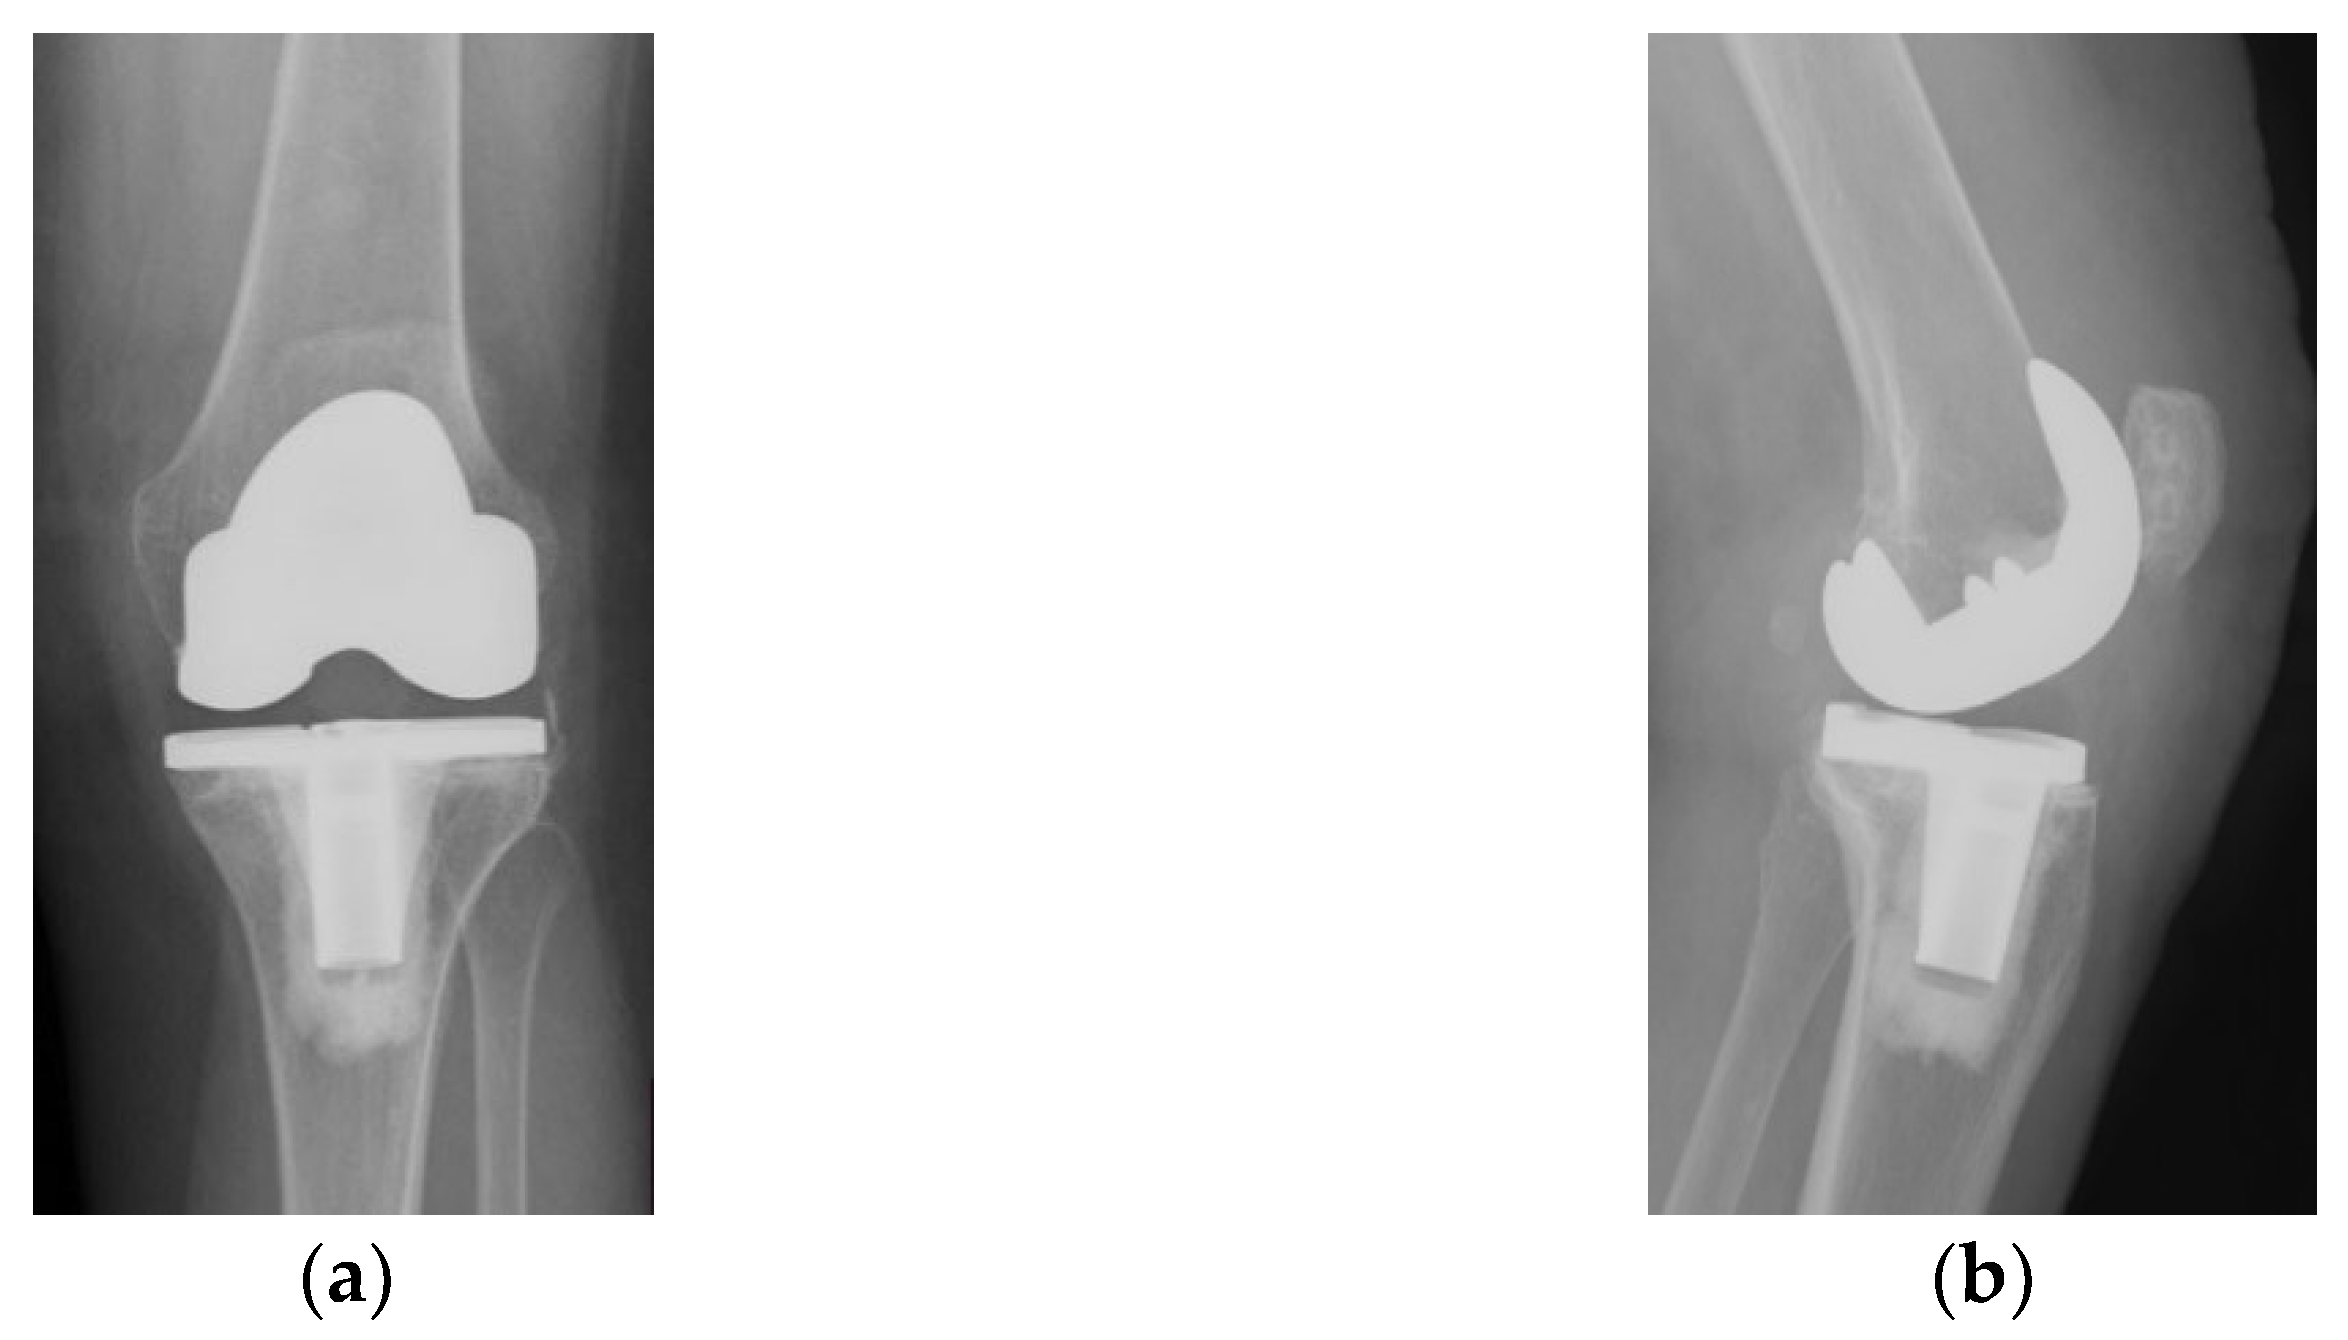

Alongside with the clinical scores, the patient was also evaluated radiologically, with CT scans and standard X-rays. Radiological investigations, using coronal, lateral and axial views (Merchant view) showed patellar arthrosis and a slight lateral subluxation of the patella (Figure 4).

Figure 4.

(a) coronal view, patellar lateral subluxation (arrow) compared to femoral axis with (1) marking the femoral trochlear axis, (2) patellar axis and (3) the patella must be centered in the femoral trochlea; (b) lateral view, patellar wear, patellar trochlea deformation and subchondral bone condensation with (4) marking subchondral osteocondensation and (5) patella bone deformation; (c) axial view, patellar lateral subluxation, and deformation, osteocondesation of the subchondral bone with (6) patella bone deformation and condensation, (7) femoral trochlear axis and (8) Patellar axis.

CT images, subject to artifacts generated by the implant, show patellar wear and peripatellar inflammatory phenomena (Figure 5).

Figure 5.

CT images: (a) Sagittal view showing patellar arthrosis, condensation of subchondral bone. (b) Axial view showing patellar arthrosis, deformation, and lateral subluxation (arrow) with (1) marking the femoral trochlear axis and (2) patellar axis; (c,d) CT 3D image, peripatellar inflammation.